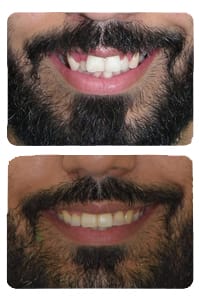

Smile-4

Anterior Cross Bite, Bimaxillary protrusion, Crocked teeth, Deep bite, Impacted teeth, Missing Teeth, Open bite, Posterior cross bite, Protruded Upper Anteriors, Smiles, Spaces between teeth, Tilted molars